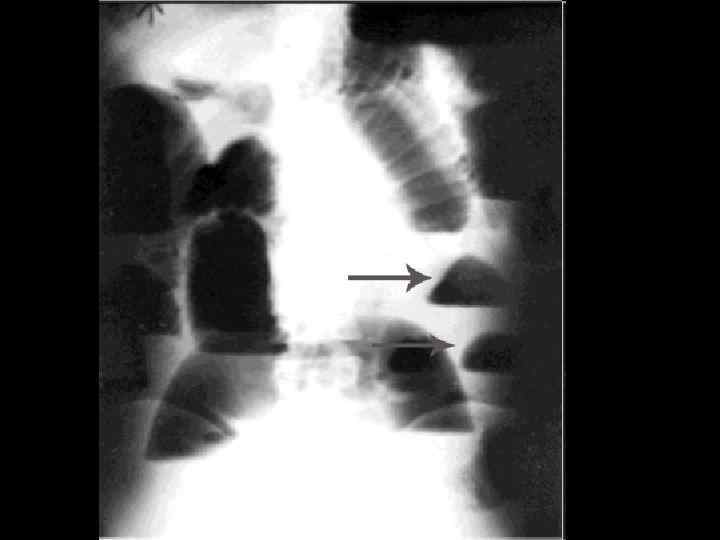

Рентгенограмма брюшной полости при тонкокишечной непроходимости. Хорошо видны спиралевидные складки слизистой оболочки, занимающие весь поперечник кишки (указаны стрелками)

Рентгенограмма брюшной полости при толстокишечной непроходимости. Видны гаустры (указаны стрелками), которые занимают лишь часть поперечника кишки